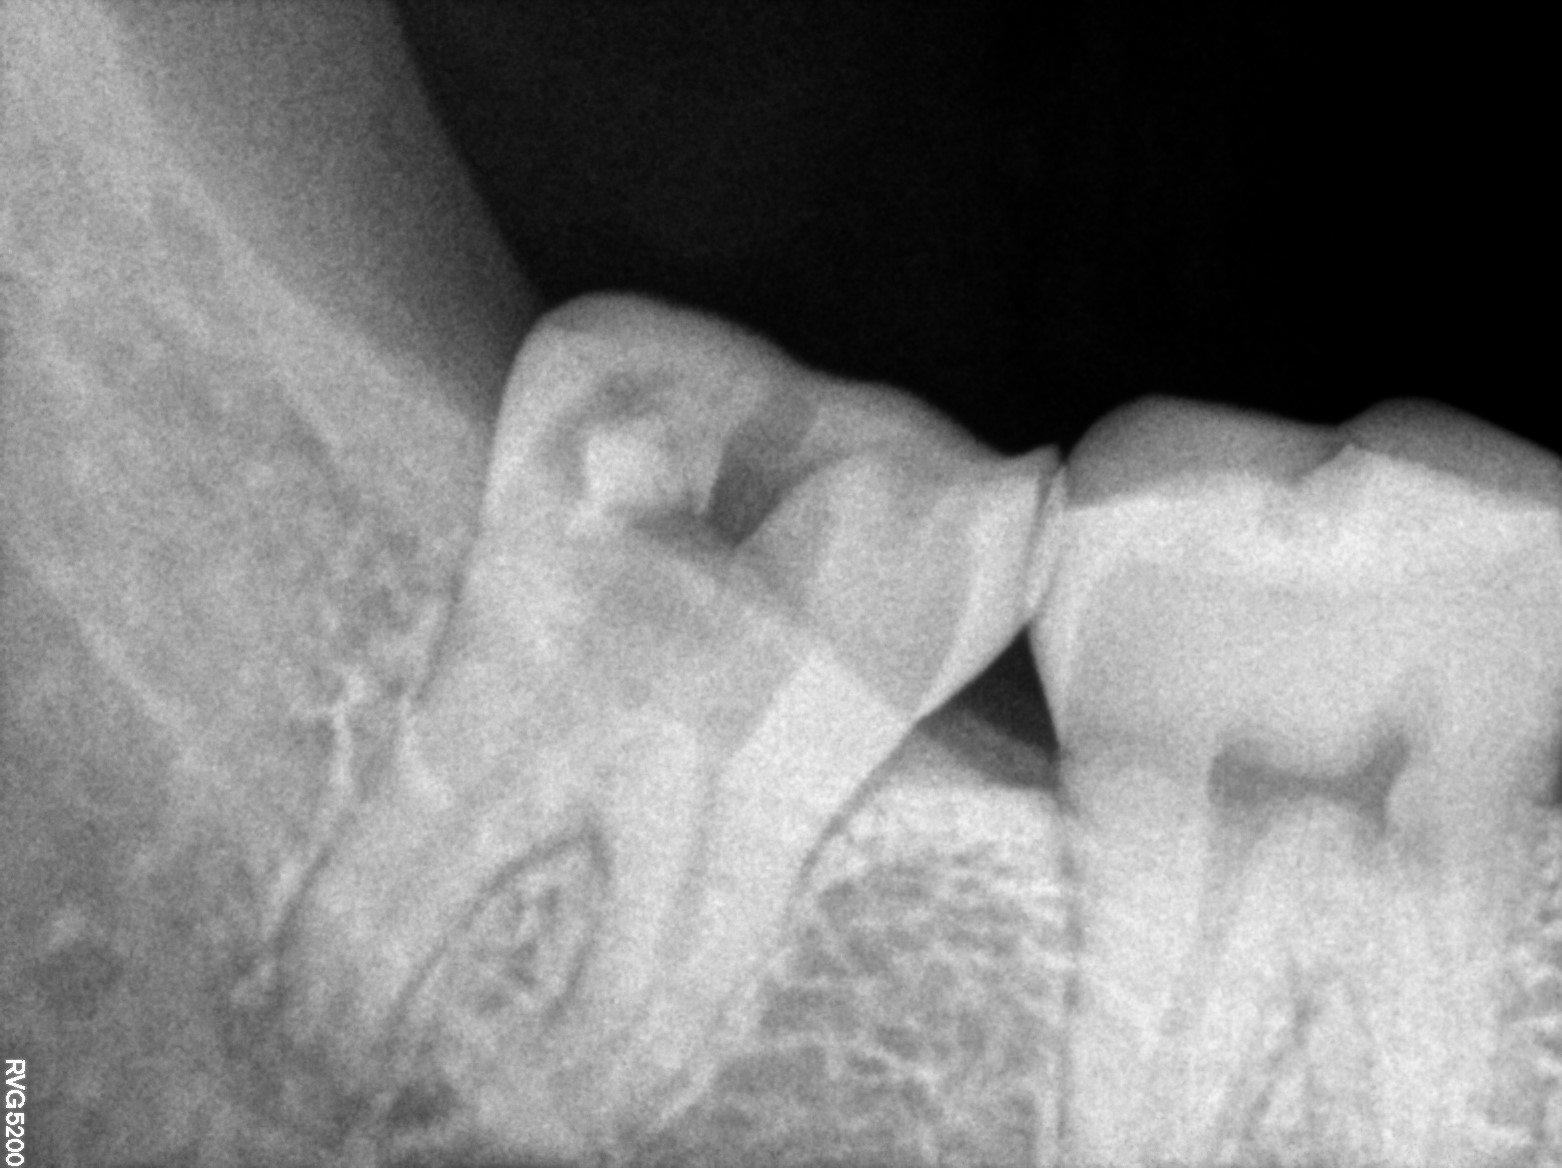

Dental Radiographs FHIR: DocumentReference · LOINC 24641-7

R61.jpg

24641-7